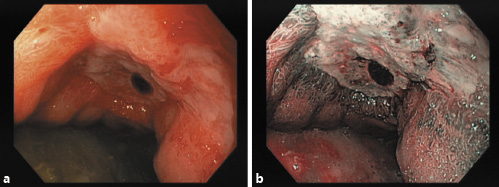

Upper endoscopy performed in the first 12 h revealed a giant gastric ulcer (30 mm) with regular borders and an adherent clot at the base - Forrest class IIb - comprising the distal third of the lesser curvature, extending through the anterior wall of the gastric body (Fig. 2); multiple biopsies were performed. The patient was discharged to outpatient consultation waiting for biopsy results and treated with pantoprazole 40 mg/day.

Fig. 2: Upper endoscopy showing a giant ulcer (30 mm) of the gastric antrum - Forrest class IIb. a Standard endoscopic view. b Narrow band imaging.